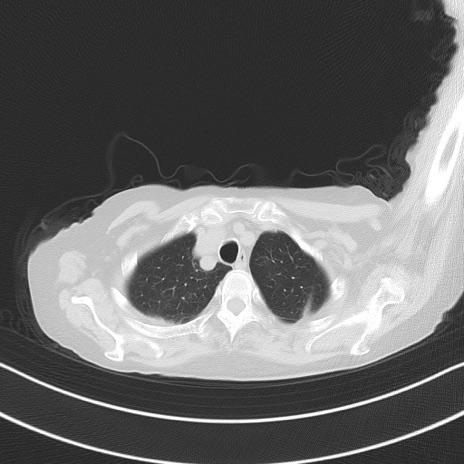

横断像

冠状断像